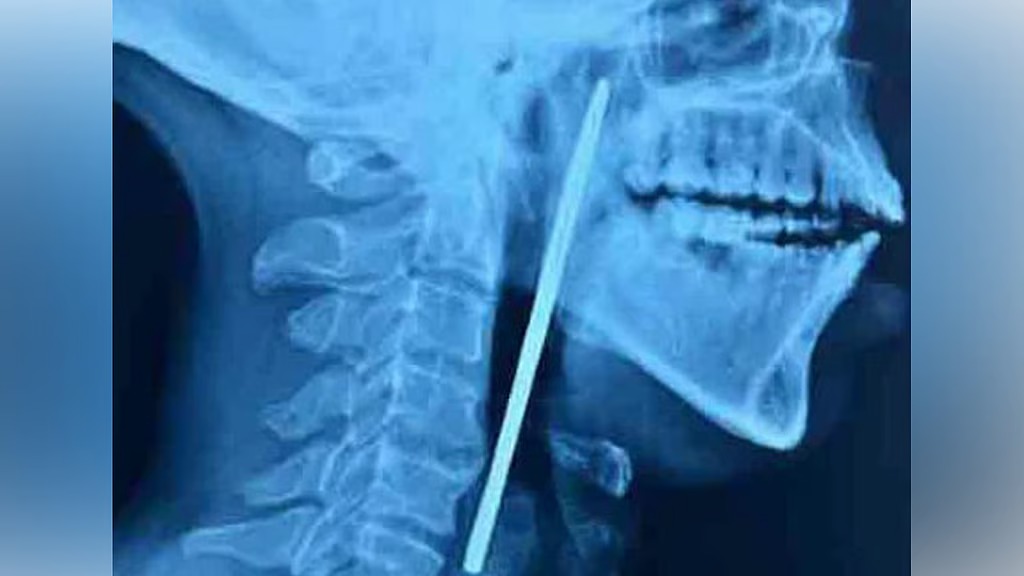

എക്സറേ പരിശോധനയില് അന്നനാളത്തില് കത്രിക കുടുങ്ങി കിടക്കുന്നതായി കണ്ടെത്തി. തുടര്ന്ന് മെഡിക്കല് കോളജ് ആശുപത്രിയില് നടത്തിയ ശസ്ത്രക്രിയയിലൂടെ 15 സെന്റി മീറ്റര് നീളമുള്ള കത്രിക പുറത്തെടുക്കുകയായിരുന്നു. ഇഎന്ടി വിഭാഗത്തിലെ ഡോ. ശ്രീജിത്തിന്റെ നേതൃത്വത്തിലാണ് ശസ്ത്രക്രിയ നടന്നത്. രോഗിയുടെ ആരോഗ്യനില തൃപ്തികരമാണെന്ന് അധികൃതര് വ്യക്തമാക്കി.